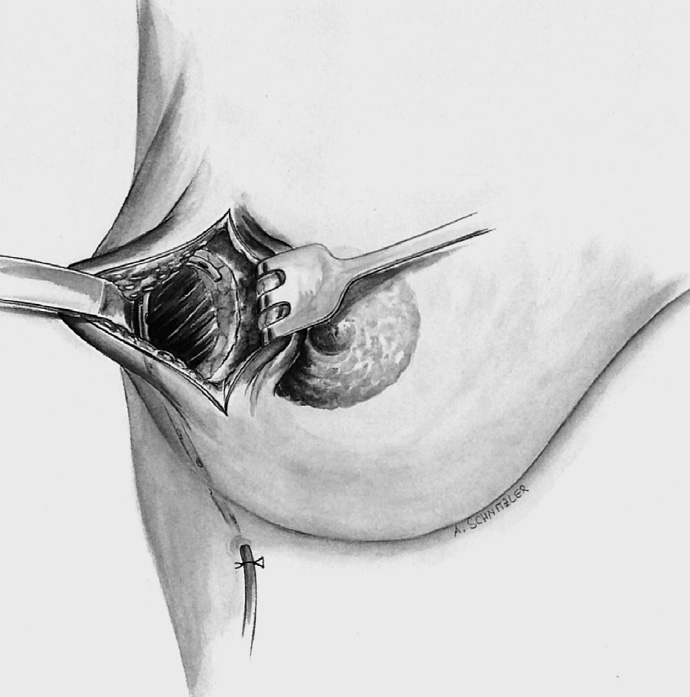

The skin is incised over the tumor region as far as possible (depending on surgeon, tumor size, tumor location, and subsequent treatment). A radial incision may be useful for tumors located in the lower quadrants or directly in the axillary tail of the breast. If the tumor is just beneath the skin, an island of skin over the tumor should be resected also. This can be achieved with both an elliptical semicircular incision and a radial incision. Another form is a purely periareolar incision when the tumor is in a relatively central position (see illustrations below).

The adjacent parenchyma is mobilized subcutaneously so that the defect can be filled with lobes of breast tissue. Mobilization means exposing the breast relative to the skin or muscle to achieve adequate mobility of < 25% or > 25% as required.

Tension-free approximation for complete intramammary cover of the defect

To cover the defect, the glandular lobes are mobilized from the adjacent parenchyma after subcutaneous dissection. The principle of intramammary lobe creation is to mobilize large parts of the breast (> 25%) either relative to the skin or relative to the pectoralis muscle. This “liberation” of the breast from one of its two planes of fixation allows adequate dissection and rotation of sufficient breast tissue. The Y-flap and rotation flap shown in Chapter 3.2.1 are examples of intramammary dissection.

When the breast is mobilized subcutaneously, it must be ensured that both the dissected skin layer and the breast tissue are sufficiently thick. For the layer of breast tissue, a minimum thickness of 1 cm is desirable. The ratio of base to length must also be considered.